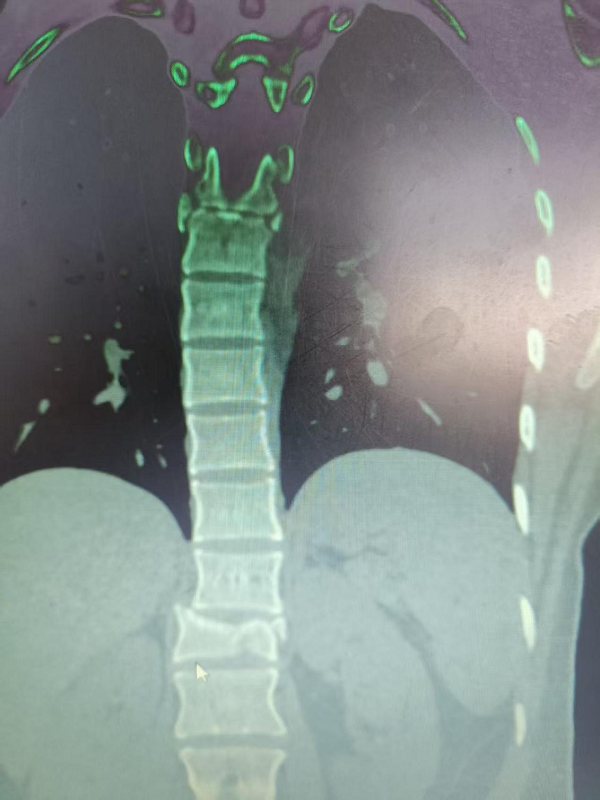

3. 为胸椎爆裂性骨折患者施后路切开复位、微创减压内固定术(四级手术),胸椎爆裂性骨折常因高能量损伤导致,骨折块可能突入椎管压迫脊髓,致残风险高。丁晔副主任医师团队采用微创理念进行减压,并完成了有效的复位与坚强的内固定,既解除了对神经的压迫,又最大程度地减少了手术创伤,为患者争取了最佳的神经功能恢复条件。